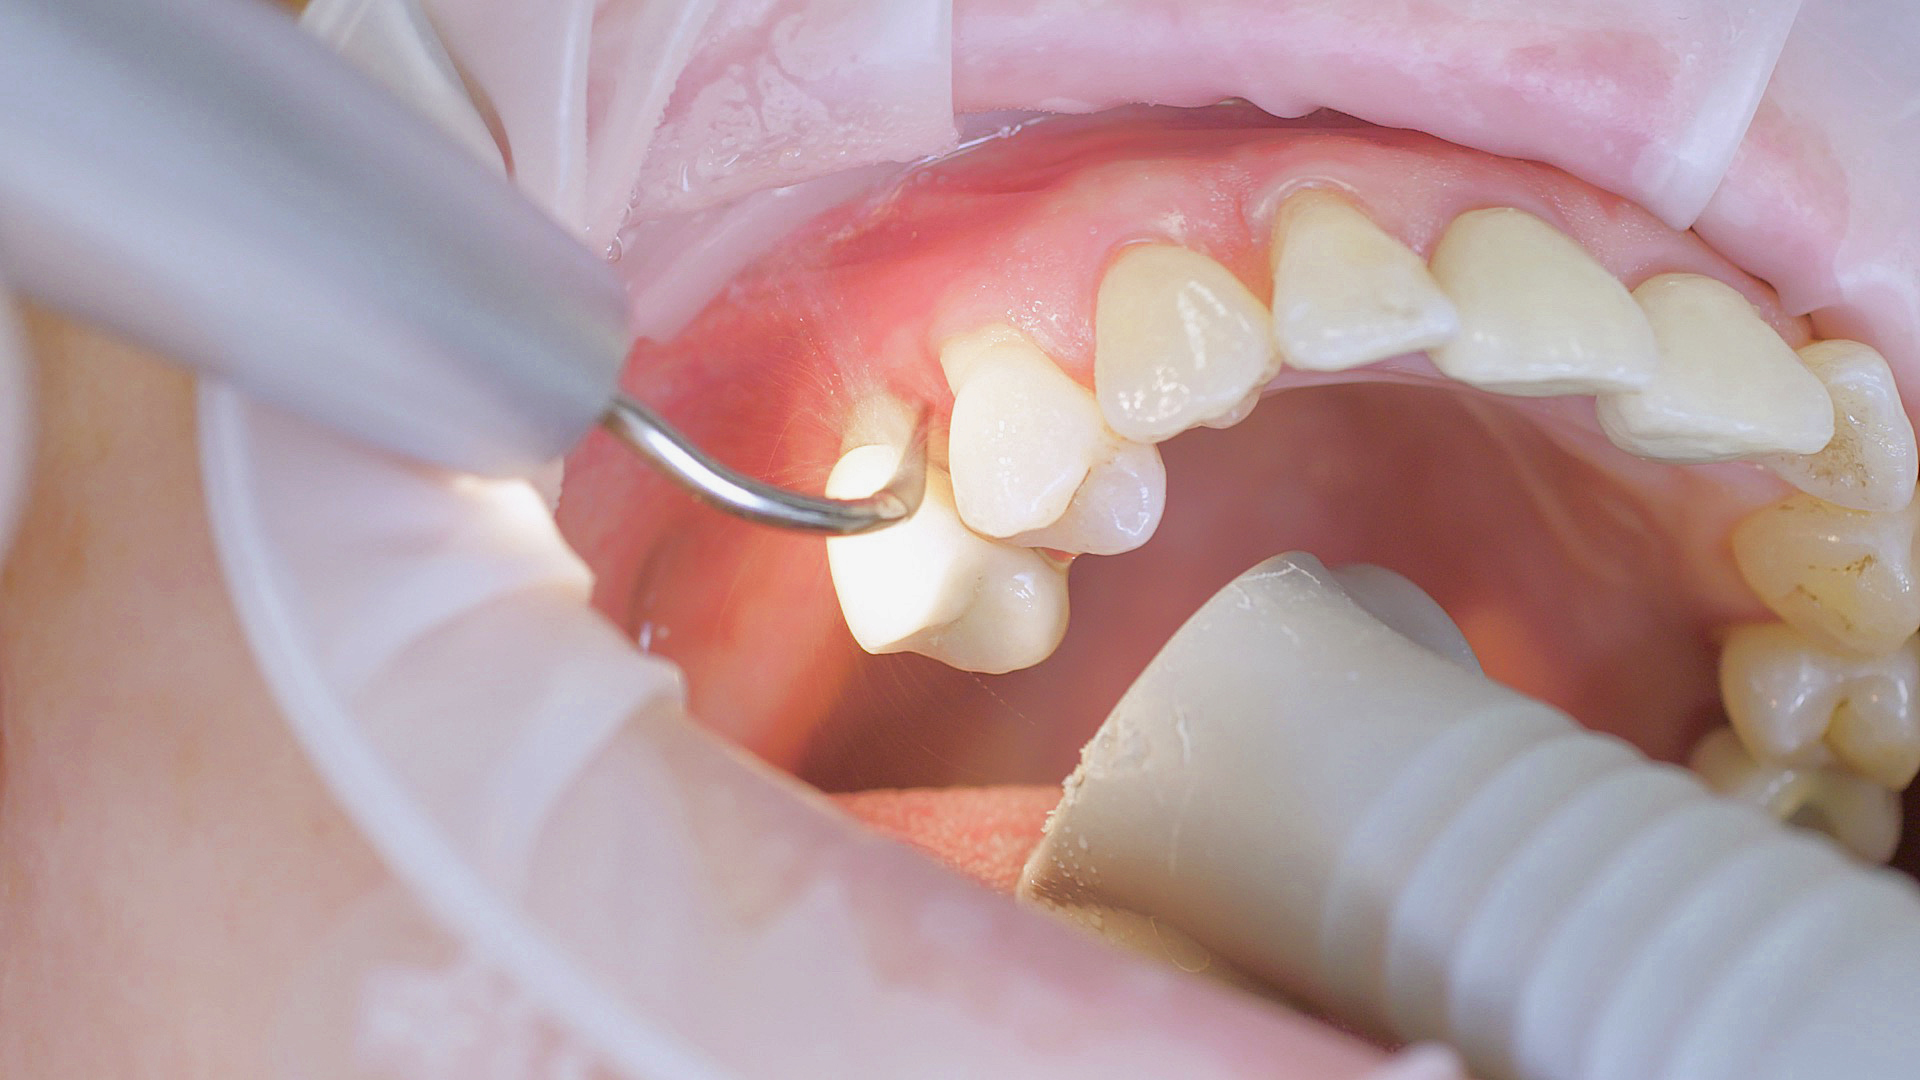

In the periodontal aftercare subsequent to implantation, soft (biofilm) and hard coatings are regularly professionally and mechanically removed.[16, 17] In the subgingival and supragingival areas, ultrasonic devices are generally used for this (Fig. 4), in combination with manual instruments where necessary. Alternatively, subgingival air polishing can be used in combination with periodontal attachments and powders.[18]